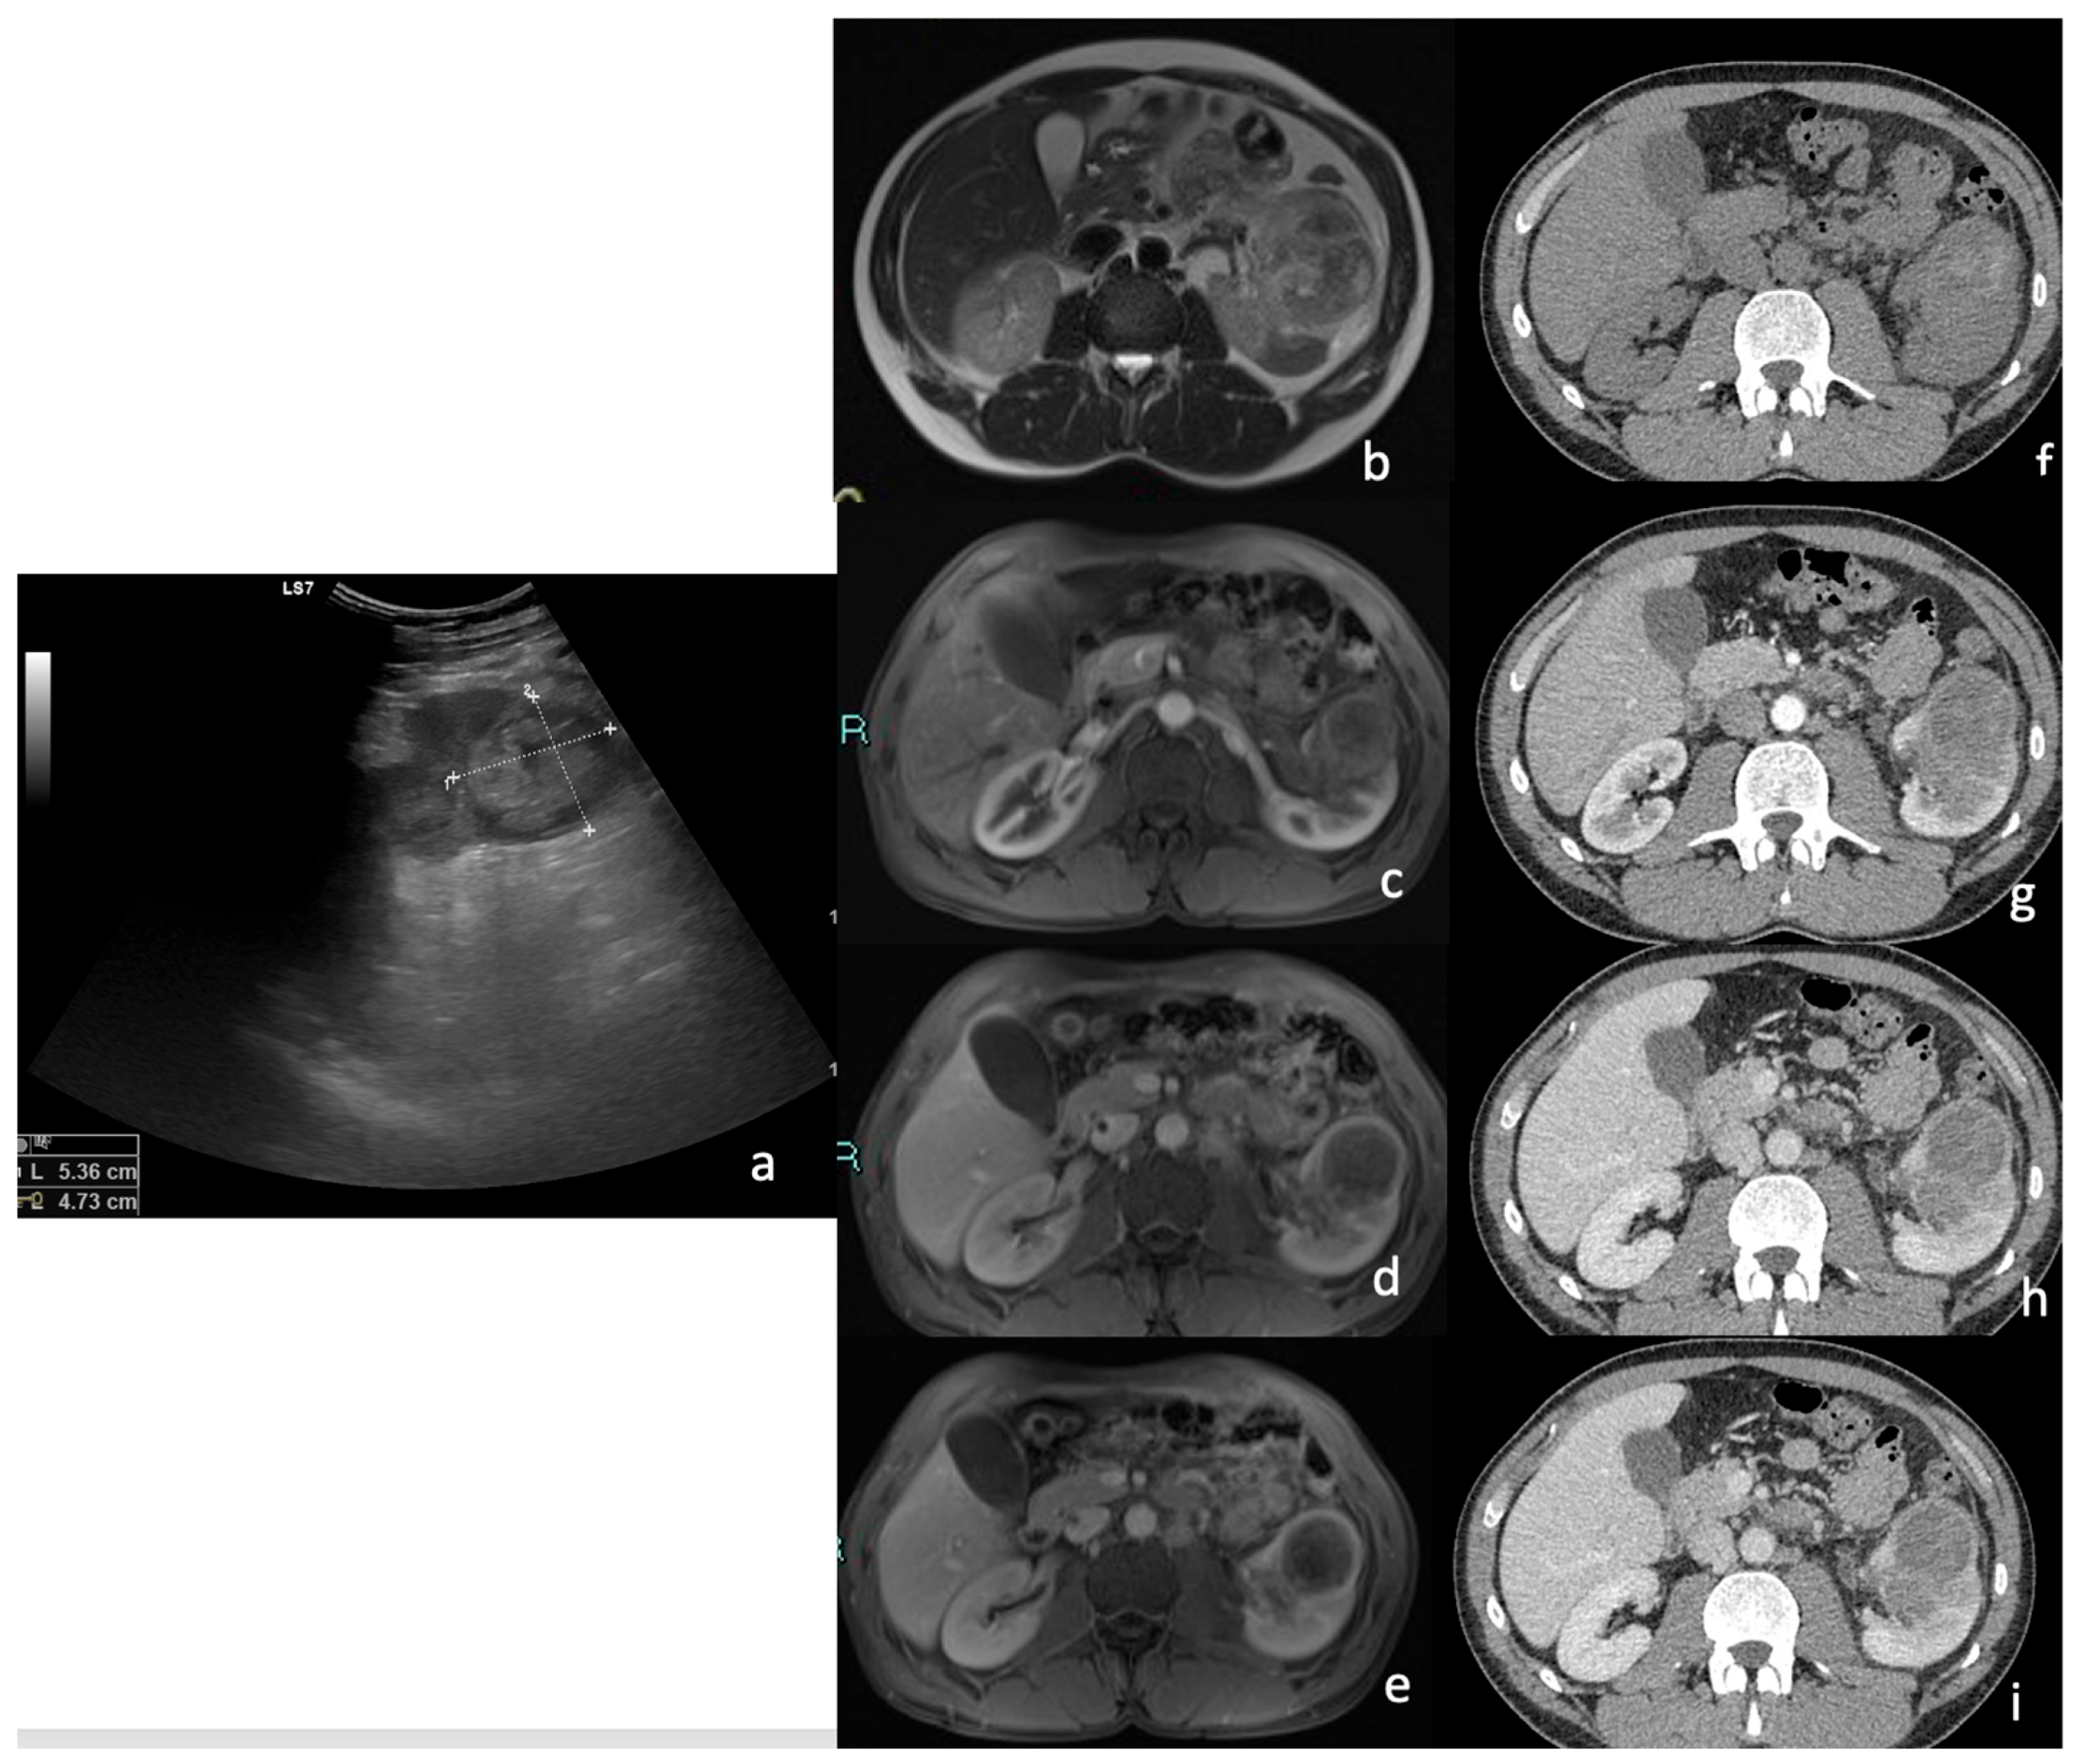

3.1. Ultrasound (US)

| Features | % | n. | p Value |

| 92.6% | 25 | p < 0.05 |

| 7.4% | 2 | p > 0.05 |

| 85.2% | 23 | p < 0.05 |

| 14.8% | 4 | p > 0.05 |

| US Features | % | n. | p Value |

| 70.3% | 19 | p < 0.05 |

| 11.1% | 3 | |

| 18.5% | 5 | p > 0.05 |

| 37.0% | 10 | p > 0.05 |